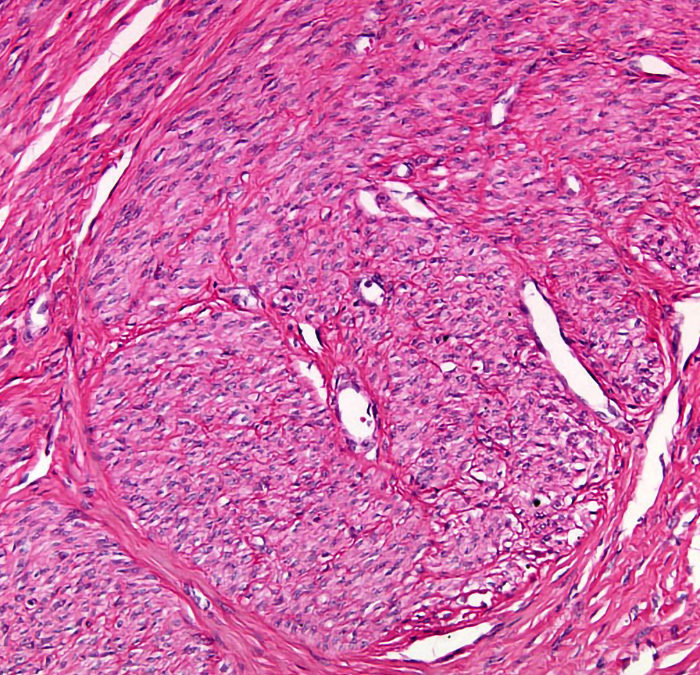

Fibroid images

by Marketing | Oct 7, 2021 | Adenomyosis, fibroids treatment, fibroids, Uterine Fibroid Embolisation, Women in White

Have you ever wondered what a uterine fibroid looks like up close? Well, here you have it under a microscope 🔬 Swipe left for a detailed schematic image showing the whorled pattern of smooth muscle bundles that make a fibroid what it is 🤓  If you’ve been diagnosed and...